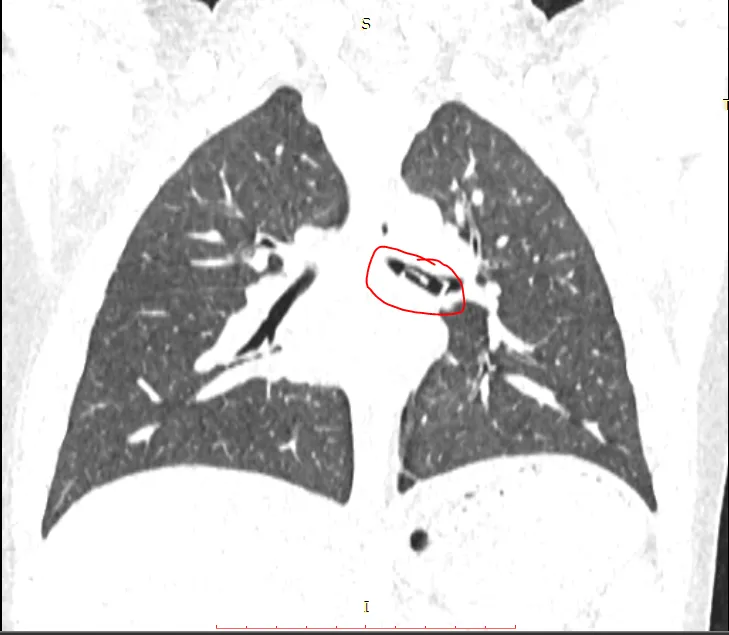

Trước đó, khoảng 11 giờ trưa 7-3, BV tiếp nhận bé trai trong tình trạng ho sặc sụa, tím tái, bứt rứt khó chịu. Người nhà kể lại bé đã nuốt nhầm đồ chơi xếp hình logo. Ngay lập tức, bệnh nhi được các bác sĩ chụp CT Scanner ghi nhận ở phế quản trái của bé có một khối dị vật hình chữ nhật, kích thước 1x2cm. Để lấy được dị vật, các bác sĩ đã quyết định thực hiện nội soi phế quản để gắp ra.

Hình ảnh CT scan xác định dị vật trong phế quản bé trai. Ảnh: BVCC